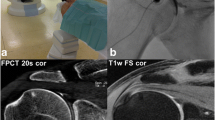

For human cadaveric joints, multiplanar reformations (MPR) were calculated from raw data in coronal, sagittal, and axial planes for both FPCT and MDCT. Slice thickness and increment were identical (1 mm and 0.6 mm respectively; Figs. 2, 3).

Coronal reformations of human cadaveric wrist arthrographies acquired with intra-articular contrast material at an iodine concentration of 45 mg/ml with FPCT a 5-s, b 8 s, c 20-s runs and d MDCT. Note increasing overall image quality and decreasing image noise for FPCT from 5 s to 20 s (a–c). The FPCT 20-s run showed comparable image quality and better depictability of anatomical structures compared with standard MDCT (d)

Coronal reformations of human cadaveric elbow arthrographies acquired with intra-articular contrast material at an iodine concentration of 45 mg/ml with FPCT a 5-s, b 8-s, c 20-s runs and d MDCT. Note increasing overall image quality and decreasing image noise for FPCT from the 5-s to the 20-s run (a–c). The FPCT 20-s run showed comparable image quality and better depictability of anatomical structures compared with standard MDCT (d)